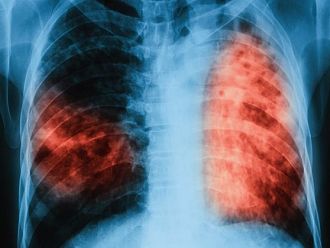

Хроничната обструктивна белодробна болест (ХОББ) е заболяване с все по—нарастваща социална значимост и според прогнозата на СЗО се очаква до 2030 г.да се превърне в третата водеща причина за смърт в световен мащаб. По официална статистика на Министерството на здравеопазването от 2018 г. между 5 и 10% от българите са с ХОББ, а едва 75 000 човека се лекуват. По неофициални данни броят на заболелите в страната е не по-малко от 500 000 души. Статистика на Европейското респираторно дружество сочи, че в Европа всяка година от ХОББ умират 300 000 души. Тези данни бяха представени по време на Национална пулмологична среща на тема “Персоналният подход в лечението на ХОББ: оптимизиране на терапията спрямо нуждите на пациента“, която се проведе в София с участието на повече от 200 пурмолози от цялата страна, както и на гост-лектори от чужбина.

Специалистите смятат, че честотата на ХОББ у нас е значително над средната за Европа и обхваща над 10% от населението над 40-годишна възраст. Причини за това са фактори като масовото активно и пасивно тютюнопушенe, замърсяването на въздуха, наличието на прах, въглероден диоксид, влага в затворените помещения и генетична предразположеност, които увреждат в значителна степен белодробната функция.